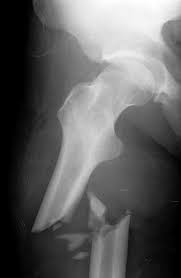

Alpha particles and beta particles are example of particulate radiation while cathode rays are beams of electrons in a partially evacuated glass tube with a potential difference between an. Our online radiology trivia quizzes can be adapted to suit your requirements for taking some of the top radiology quizzes. First, you need to identify the fractures inside the body. May 21, 2018 · radiology questions and answers (q&a) what is an example of particulate radiation? Dec 05, 2017 · more radiology quizzes oral radiology examination practice test! This quiz will test the dental student's understanding and knowledge of radiation physics and the fundamentals of radiographic interpretation. Apr 06, 2021 · a comprehensive database of more than 14 radiology quizzes online, test your knowledge with radiology quiz questions. Next, you need to diagnose the underlying condition.

First, you need to identify the fractures inside the body.